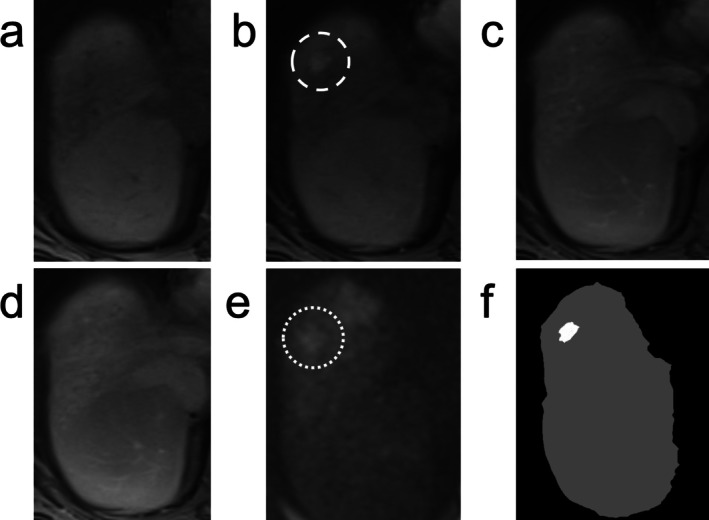

美国放射学会肝脏影像学报告和数据系统(LI-RADS)是对肝细胞癌高危患者肝脏影像学观察进行分类和风险分层的卓越框架。本文综述了肝细胞癌的发病机制和MRI在LI-RADS中的应用,具体包括LI-RADS诊断算法,其组成部分,以及参考最新支持证据的可重复性。综述了LI-RADS治疗反应算法,包括最近的放射治疗反应算法。探讨了人工智能的应用,争议点,LI-RADS相对于其他肝脏成像系统,以及可能的未来方向。通过阅读本文,读者将对LI-RADS的基础和应用以及可能的未来方向有一个了解。

The American College of Radiology Liver Imaging Reporting and Data System (LI-RADS) is the preeminent framework for classification and risk stratification of liver observations on imaging in patients at high risk for hepatocellular carcinoma. In this review, the pathogenesis of hepatocellular carcinoma and the use of MRI in LI-RADS is discussed, including specifically the LI-RADS diagnostic algorithm, its components, and its reproducibility with reference to the latest supporting evidence. The LI-RADS treatment response algorithms are reviewed, including the more recent radiation treatment response algorithm. The application of artificial intelligence, points of controversy, LI-RADS relative to other liver imaging systems, and possible future directions are explored. After reading this article, the reader will have an understanding of the foundation and application of LI-RADS as well as possible future directions.